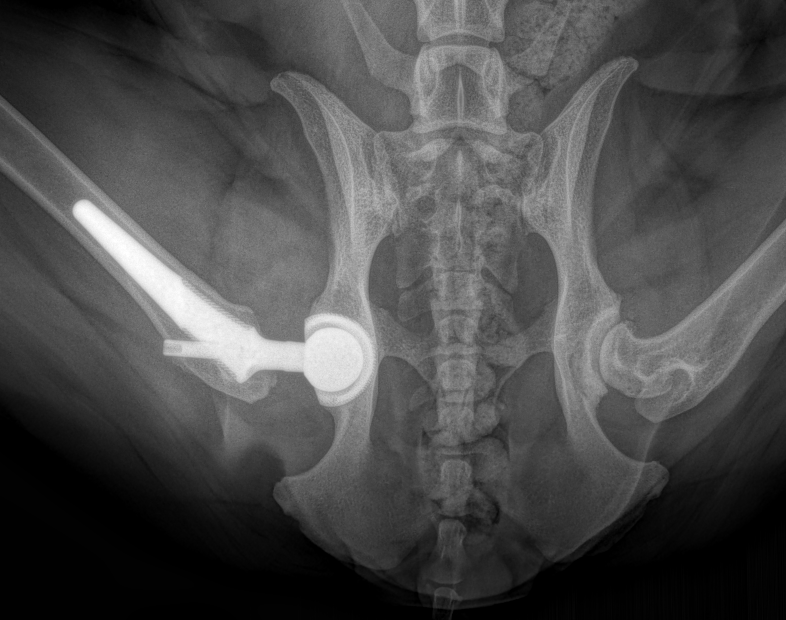

A "frog leg" ventrodorsal radiograph of a hybrid total hip replacement. A "hybrid" hip combines both uncemented and cemented prosthesis components. In this case, the acetabular cup is a Biomedtrix BFX uncemented cup and will allow for bone ingrowth/ongrowth and a biologic fixation. The femoral component is a Biomedtrix CFX cemented stem with use of a restrictor plug.